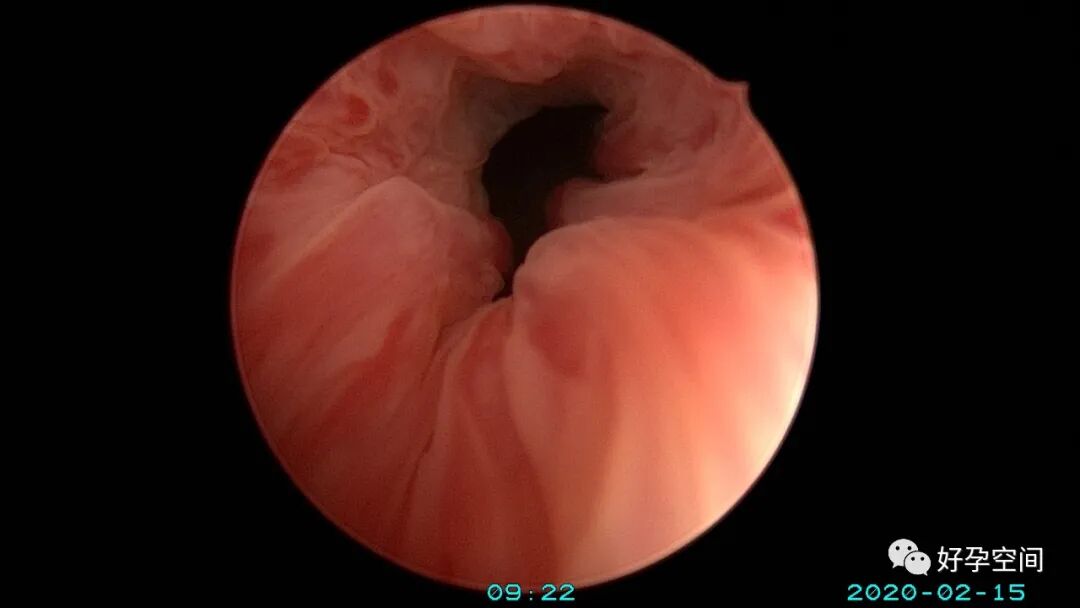

病例5:48岁,开腹子宫全切术后膀胱阴道瘘,阴式膀胱阴道瘘修补,宫腔镜探查阴道穹窿、探查膀胱、输尿管置管。